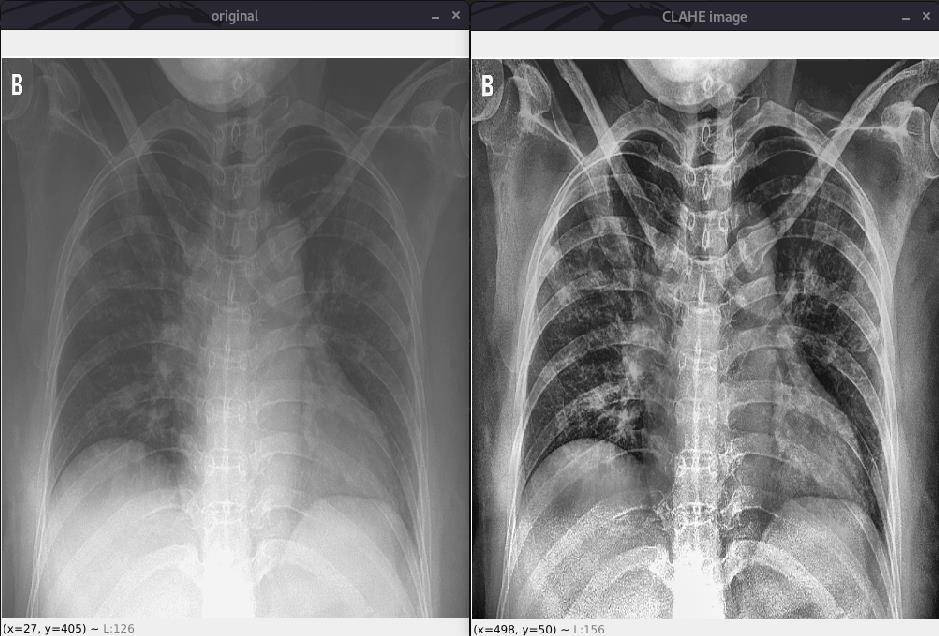

• CLAHE limits the amplification by clipping the histogram at a predefined value before computing

the CDF.

• In this we limit the slope of transformation function by a so called clip limit.

• It is advantageous not to discard the part of the histogram that exceeds the clip limit but to

redistribute it equally among all histogram bins